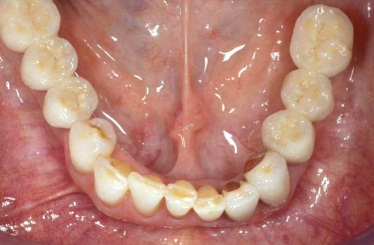

Náhrada jednoho zubu pomocí implantátu je možná také v postranním úseku chrupu. Při ztrátě většího počtu zubů ve frontálním nebo postranním úseku může být mezer uzavřena větším počtem jednotlivých implantátů.

Při ošetření pomocí jednotlivých implantátů zůstávají sousední zuby neporušené – intaktní. Při klasickém ošetření pomocí můstků musejí být tyto zuby obroušeny!